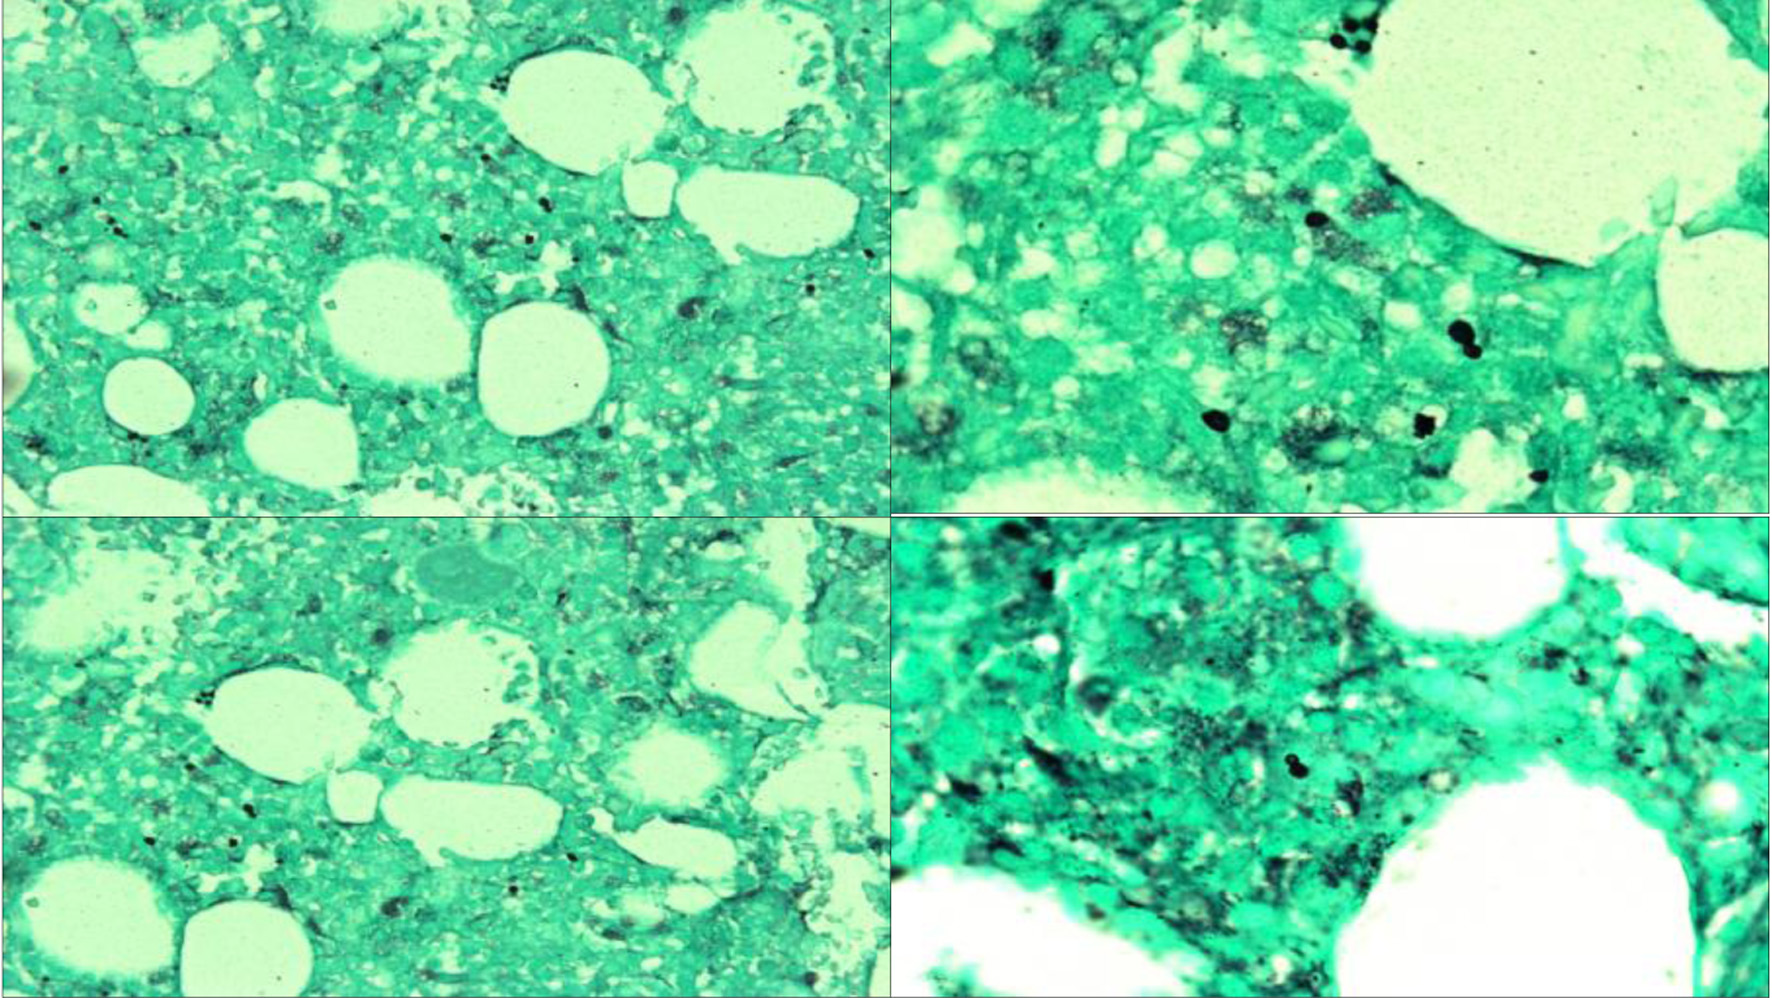

Upon arrival, Infectious Diseases discontinued antimicrobials, given that the patient had not had improvement after 2 weeks, and ordered a (1-3)-β-D-glucan (Fungitell) test. Hematology and Oncology were consulted for concern of HLH given persistent fever, cytopenias, coagulopathy, elevated ferritin, and hypertriglyceridemia. Bone marrow biopsy histopathology (Fig. 1) showed hypercellular bone marrow with histiocytosis and occasional hemophagocytic forms (Fig. 2) as well as intracellular narrow-based budding yeast (Fig. 3), consistent with HLH and suggestive of disseminated histoplasmosis. A positive Fungitell later confirmed systemic fungal infection and sIL2R was markedly elevated at 10,324 U/mL (reference range: < 1,033 U/mL), fulfilling HLH-2004 criteria [4] (Table 1).

Figure 1. Bone marrow core biopsy histopathology. (a) H&E staining at × 20 magnification showing hypercellular marrow (60% cellularity). (b) CD68 staining diffusely positive showing histiocytosis (right upper). (c) Wright-Giemsa staining at × 100 magnification showing erythrophagocytic forms and hemophagocytic forms with ingested leukocytes (lower left). (d) GMS staining showing narrow-based budding yeasts consistent with histoplasma capsulatum (right lower). GMS: Grocott-Gomori methenamine silver; H&E: hematoxylin and eosin.

Figure 3. GMS staining at × 40 (upper left, lower left) and × 100 (upper right, lower right) showing numerous extracellular small narrow-based yeast cells consistent with disseminated histoplasmosis. GMS: Grocott-Gomori methenamine silver.